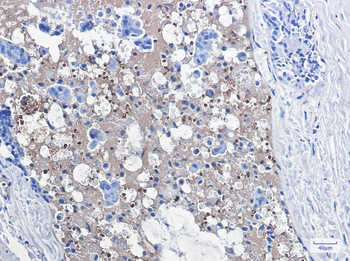

Immunohistochemistry of Catalase in paraffin-embedded Human breast cancer tissue using Catalase Rabbit mAb at dilution 1/1.